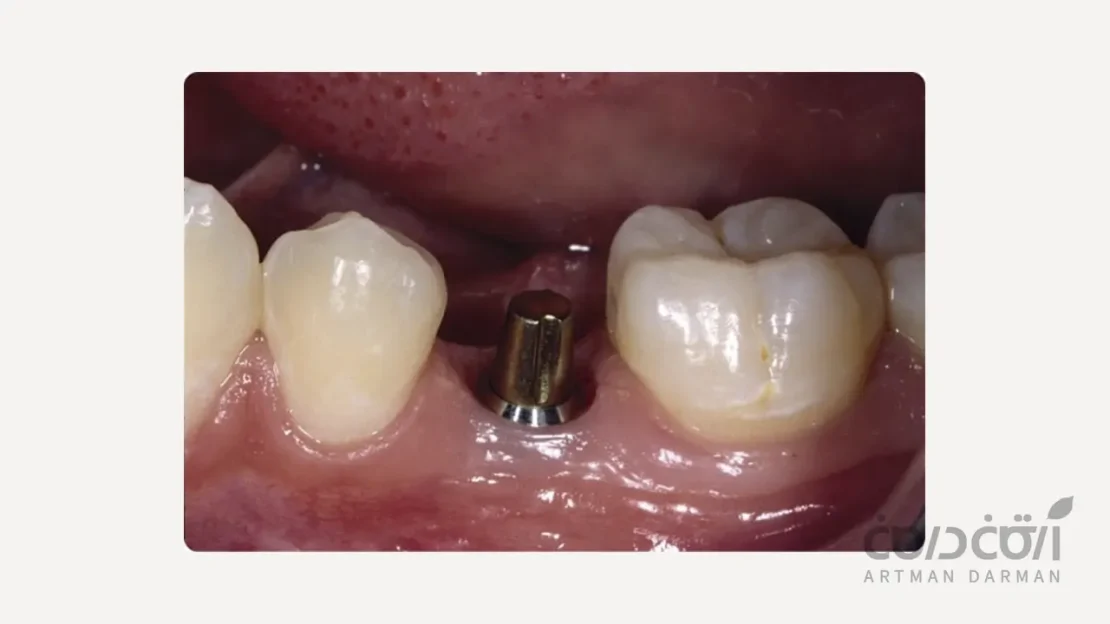

اباتمنت یا رابط پروتزی

این قطعه، یک رابط دقیق است که پس از دوره ریکاوری، روی پایه ایمپلنت سوار می شود. اباتمنت از لثه بیرون میزند و به عنوان پایه ای عمل می کند که روکش نهایی روی آن قرار می گیرد.

اباتمنت ها در اشکال، زوایا و جنس های مختلف (تیتانیوم یا زیرکونیا) وجود دارند تا دندانپزشک بتواند بهترین نتیجه پروتزی را حتی در شرایط آناتومیک پیچیده، به صورت سفارشی برای شما ایجاد کند.

گام چهارم و پنجم به ساخت بخش پروتزی اختصاص دارد

پس از اطمینان از جوش خوردن کامل ایمپلنت به استخوان، مرحله پروتزی آغاز می شود. با یک جراحی کوچک، سر ایمپلنت نمایان شده و اباتمنت روی آن بسته میشود. سپس، یک قالب گیری دقیق (به روش سنتی یا با اسکنر دیجیتال) از اباتمنت و دندان های مجاور گرفته می شود.

در نهایت لابراتوار بر اساس این قالب، یک روکش سرامیکی کاملاً سفارشی می سازد که در جلسه نهایی، روی اباتمنت نصب شده و درمان شما کامل می شود.